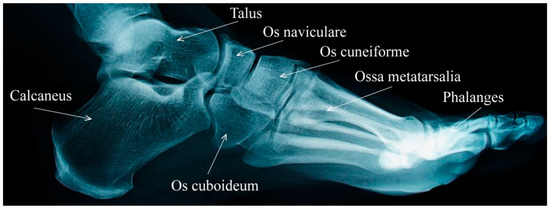

2. Numerical Bone Modelling